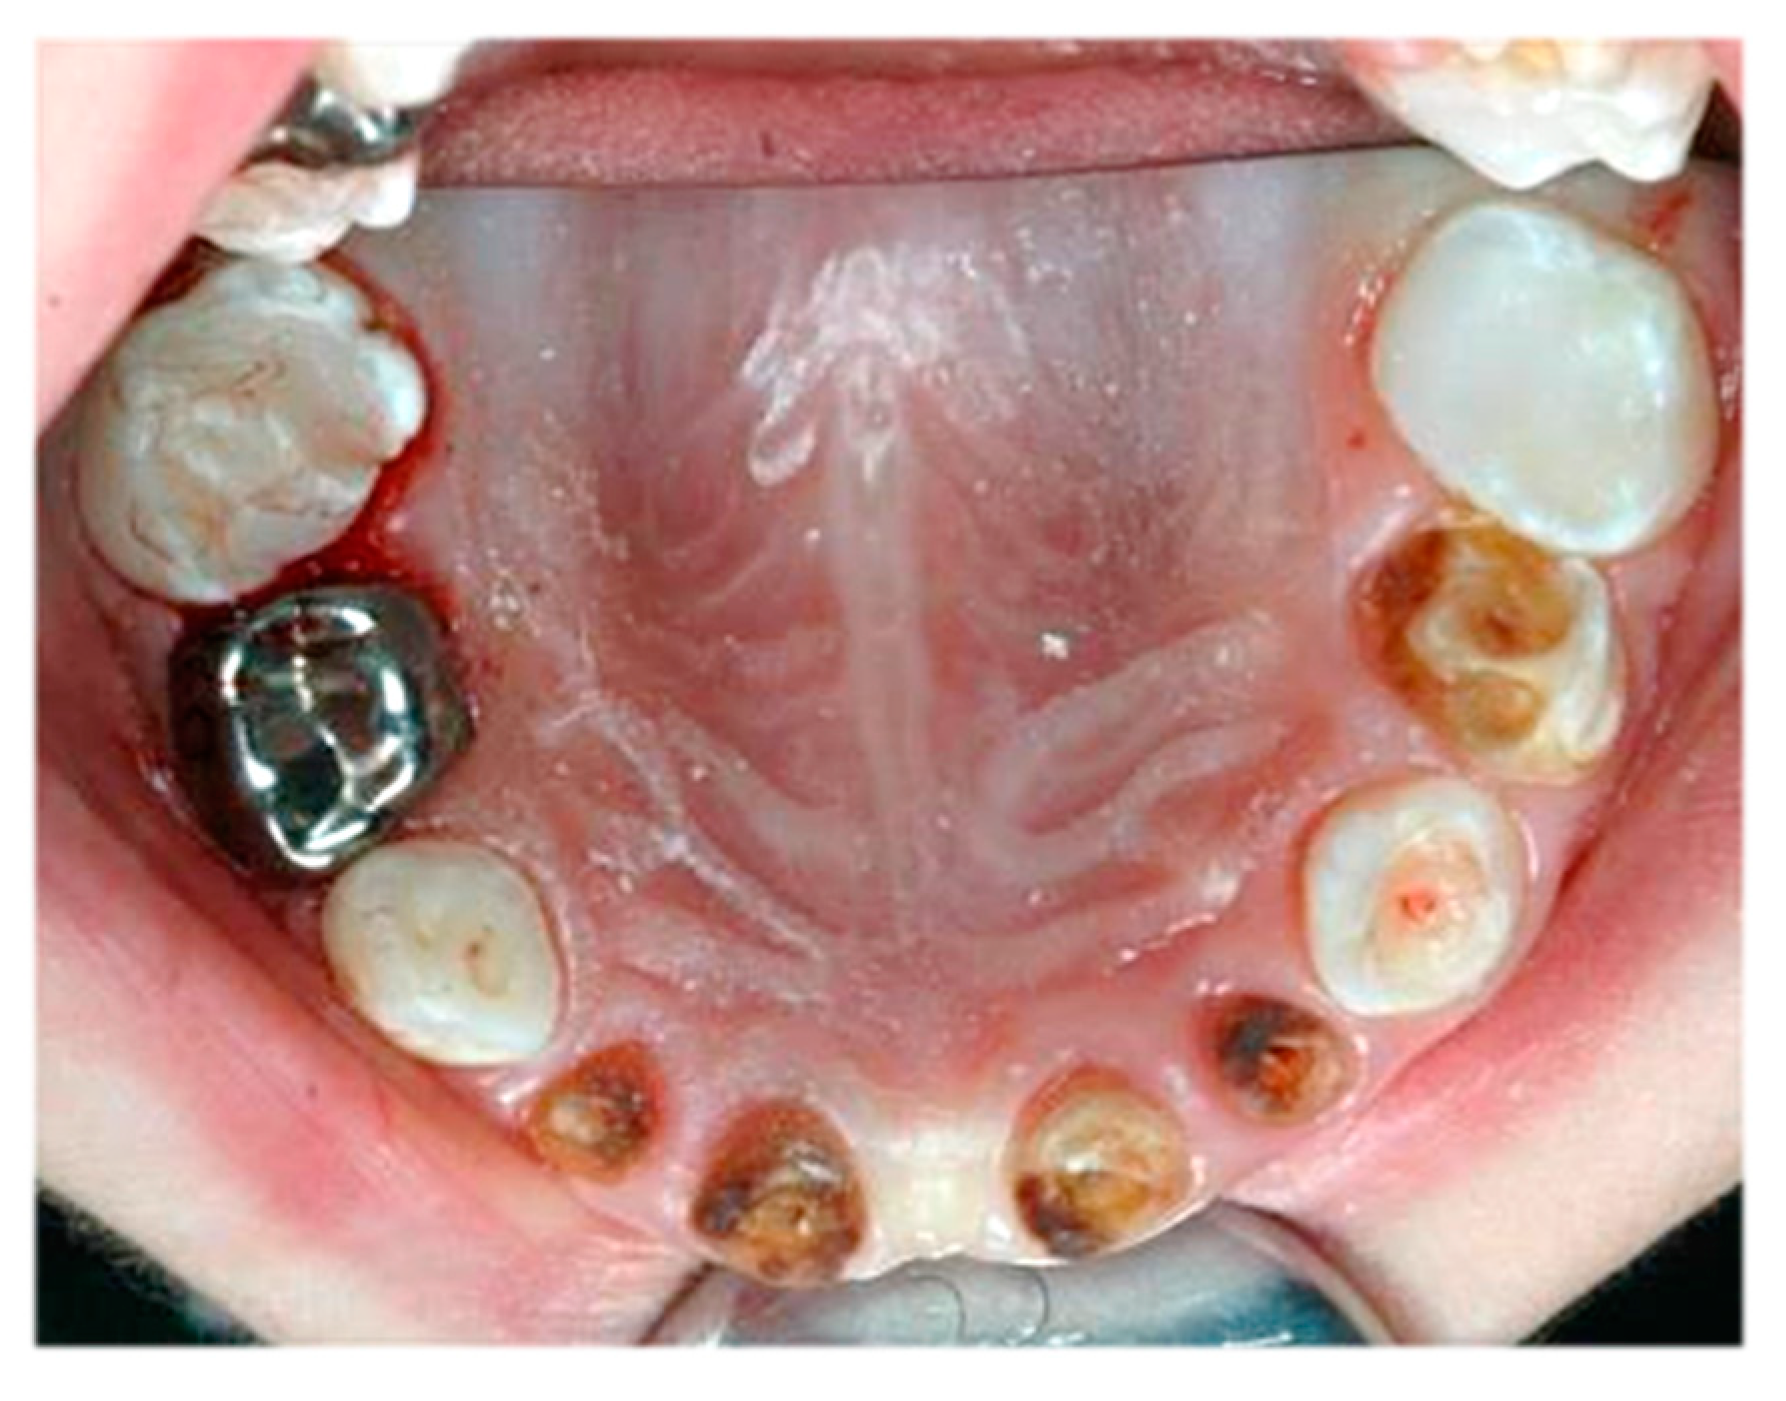

In total, 14 children (40%) only received fillings, while two or three further procedures were performed in 21 children (60%). An example of the dentition of a child requiring multiple dental procedures is shown in Figure 3.

Figure 3. Severe early childhood caries in the primary maxillary teeth of a child requiring several types of dental treatment under general anaesthesia.